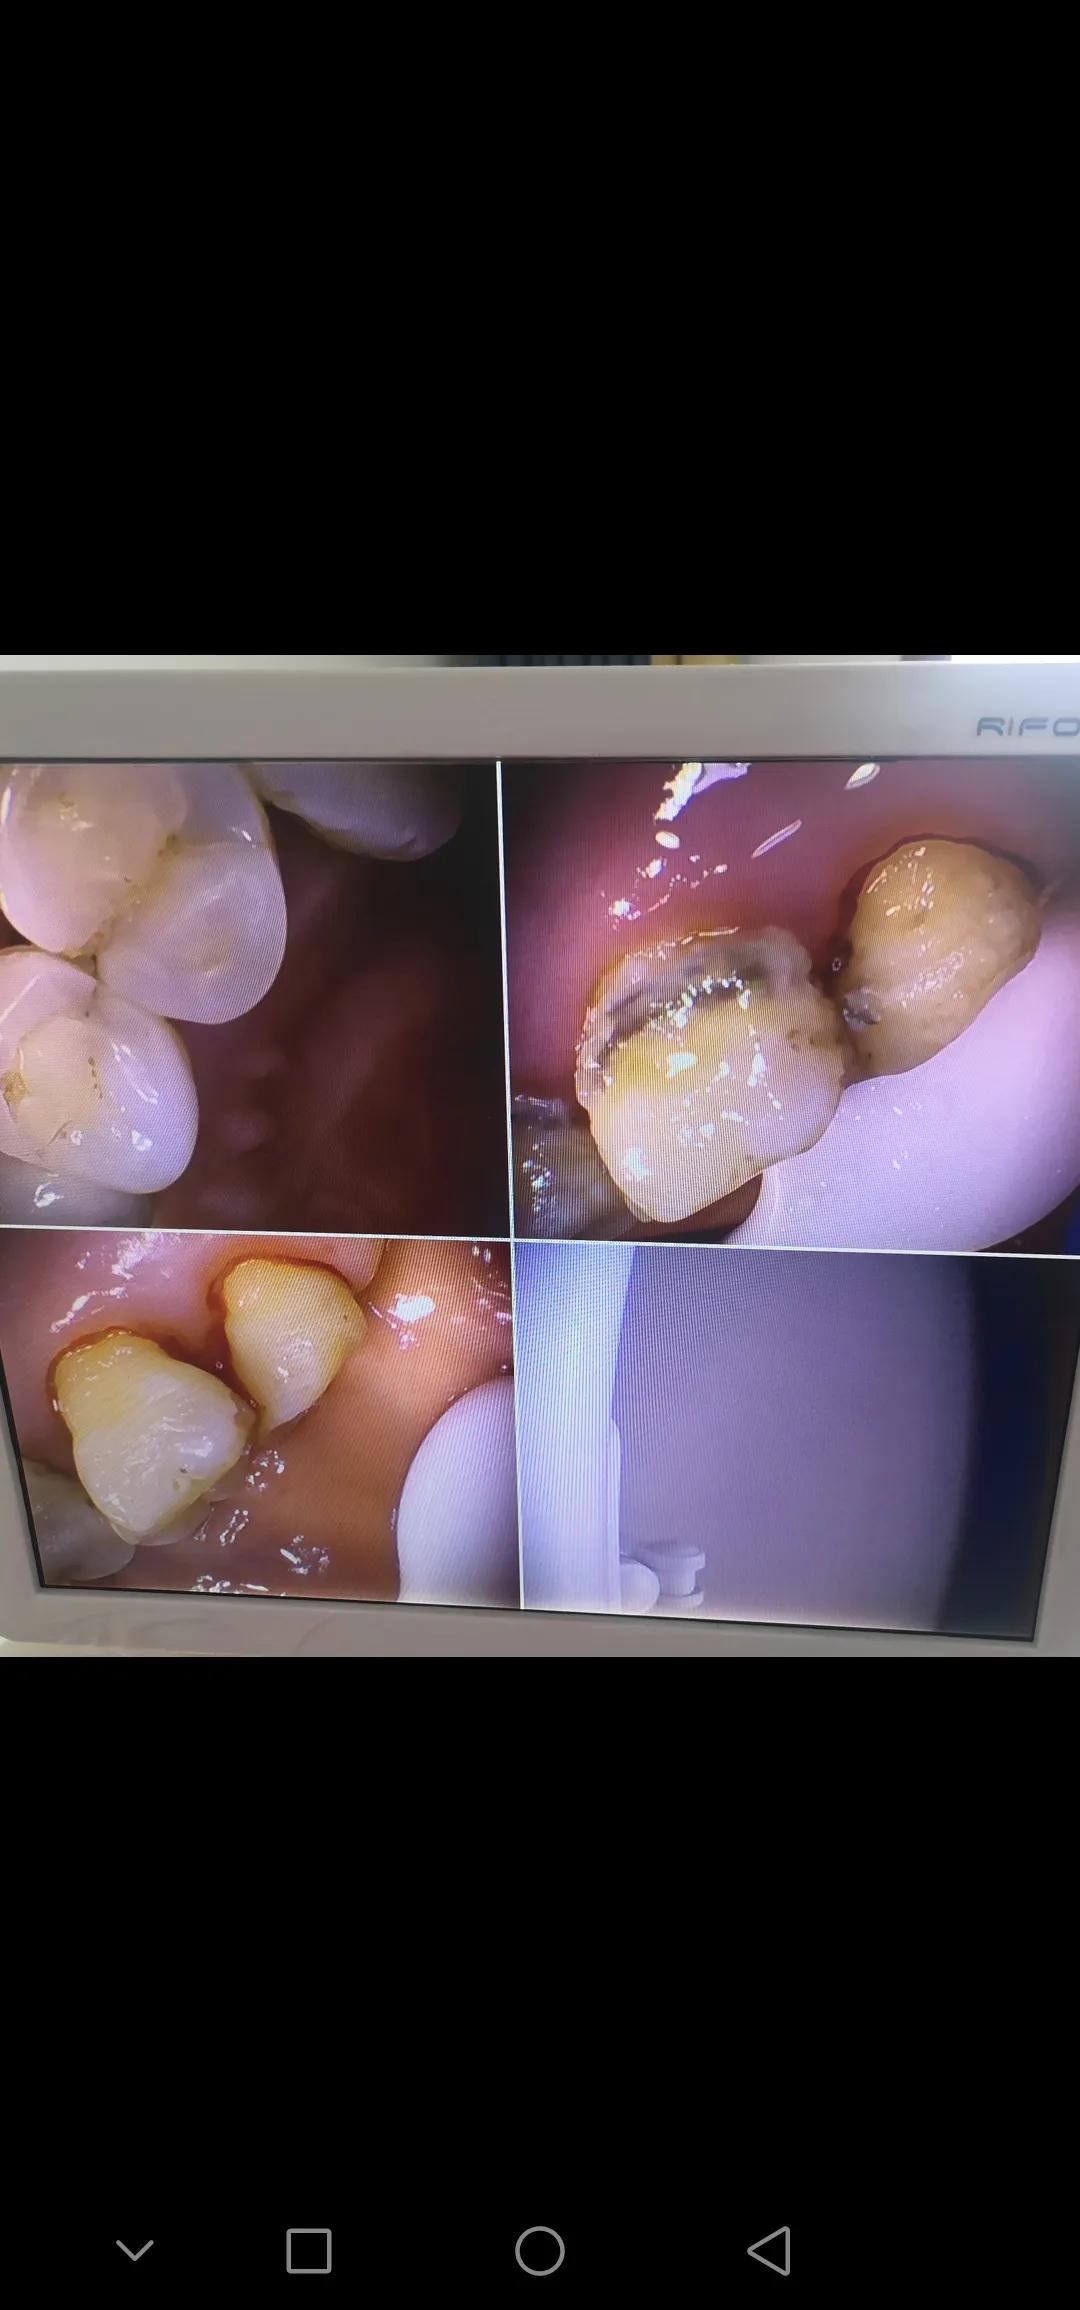

这是牙科椅配的内窥镜拍出来的洗牙前后的对比,先放上来让大家有个印象,我们之后会讲刷牙,洗牙等,希望能够有用!